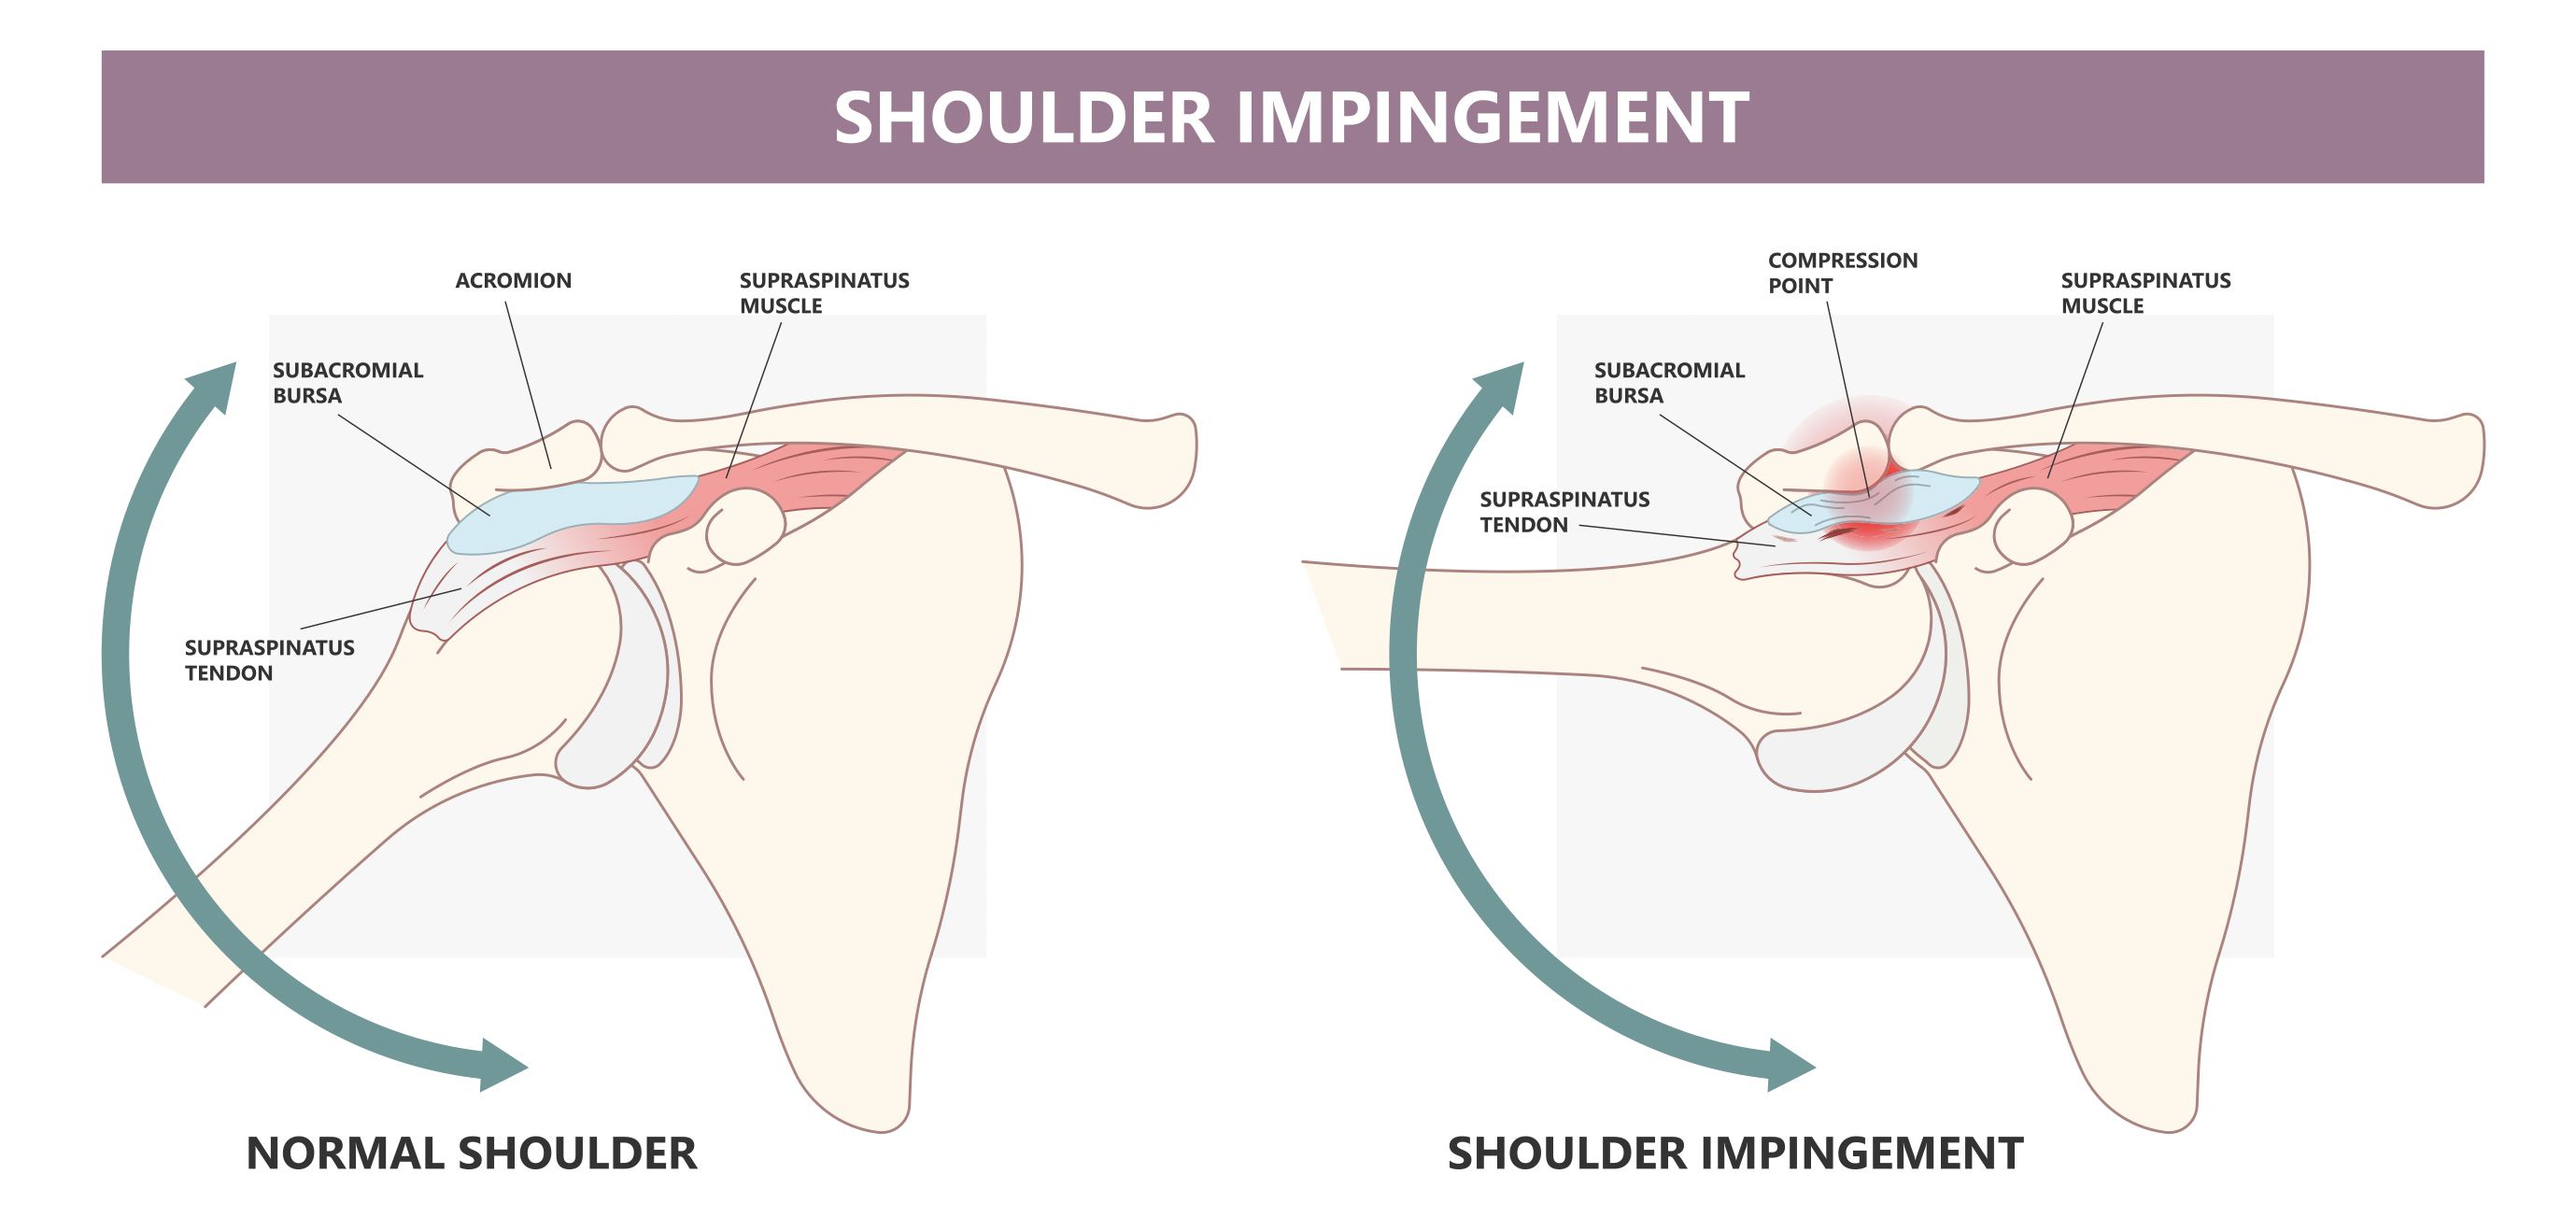

Rotator Cuff Pain: K Tape + Rehab Short-Term Effects

Nguyen, T. N. A., Nguyen, N. H., Vu, D. K., & Cu, L. T. N. (2025). Short-term effects ofKinesiotaping combined with a rehabilitation program for rotator cuff-related shoulder pain: Arandomized, ...

Rotator Cuff Pain: K Tape + Rehab Short-Term Effects

Nguyen, T. N. A., Nguyen, N. H., Vu, D. K., & Cu, L. T. N. (2025). Short-term effects ofKinesiotaping combined with a rehabilitation program for ...

肩痛:保守治疗的有效性

参考文献:Steuri, R.、Sattelmayer, M.、Elsig, S.、Kolly, C.、Tal, A.、Taeymans, J. 和 Hilfiker, R. (2017)。保守干预措施(包括运动、手法治疗)的有效性......